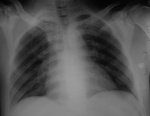

Мужчина 31 г., множественные ножевые ранения боковой стенки живота и грудной клетки справа.

Что можно сказать по данному снимку (на вторые сутки после травмы, сидя)?

Снимок на выдохе или не глубоком вдохе ( боль) искали пневмоторакс. Не отведенные лопатки. Расширение верхнего средостения справа, думаю связано с поворотом. Плотные очаги. Интерес ко 2 межреберью справа, фокусная тень?. Боковой, рентен контроль.

Вроде страшного ничего нет. Смущает расширение верхнего средостения вправо, видимо вследствие укладки. Предположу добавочную долю v.azygos

Как Вы думаете, почему приличный объем жидкости на прямом снимке выглядет необычно? Нет линзообразного контура, горизонтального уровня, контуры "диафрагмы" четкие, а объем жидкости около 500 мл по КТ и результатам торокацентеза (все, снимок, кт, центез в один день).

По прямой рентгенограмме жидкость вообще бы не описал, ее можно только предполагать, зная анамнез ножевого ранения гр.клетки. Горизонтальный уровень будет тогда, когда будет еще и воздух в плевральной полости, Обычно четкая диафрагма(по прямой рентгеограмме) наблюдается когда жидкости менее 200мл, здесь чекая диафрагма и больший объем жидкости обусловлен малым вдохом( или рентген на выдохе).Развейте сомнения ( или подтвердите) по поводу добавочной доли v. azygos, у Вас есть КТ.

Видимо гемоторакс. Не свободная жидкость, по задней поверхности, поэтому может так выглядеть на прямом снимке. Легочная ткань частично "минусует" интенсивность затемнения на R-грамме.

Мне кажется, жидкость свободная, растекается по КТ, несоответствие картины прямой рентгенограммы и КТ. Да и вторые сутки, жидкость плотная, ниже уровня диафрагммы, да и торакоцентез.

500 мл не всегда можно увидеть на снимках ОГК в нестандартном положении, да ещё в одной проекции. Где-то у Линденбратена написано что 500 мл можно увидеть только закрытие синуса. Хорошо, что не остановились на одном снимке, а сделали ряд диагностических исследований. Только непонятно, почему КТ сразу не провели?

С чем связана необычная визуализация гемоторакса на прямом вертикальном снимке? Нет линзообразного затемнения, горизонтального уровня, контуры диафрагмы четкие - почему?

Именно из-за того, что гидроторакс выглядет как контур диафрагмы, что не совсем привычно и должно иметь какое то объяснение и был приведен данный случай.

На первом и последнем снимке, где нет гидроторакса контур правого купола одинаковый - сферичный к синусу, а на 3 и 4 снимке гидроторакс иммитирует контур диафрагмы своей четкостью, но выдает себя конфигурацией у синуса....

Согласен .... УЗИ дважды видит 500 мл, по КТ видно 500 мл, при дренировании - вышло 500 мл.... почему эти 500 мл на качественном третьем снимке выглядят именно так - клинообразной полоской затемнения над куполом диафрагмы? Основание клина направлено к правому синусу.